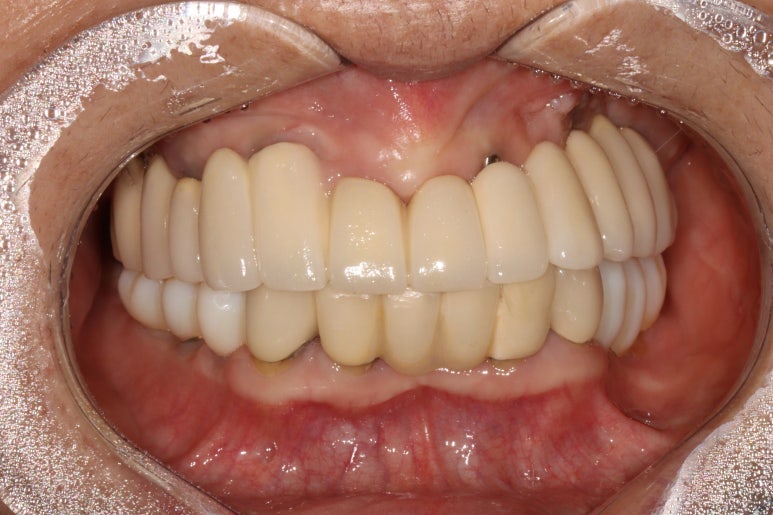

저희 치과와 협업하는 기공소에서 제작해온 임시치아를 장착한 상태입니다.

플라스틱 재질인 레진으로 제작되어 있어 색상은 그닥 수려하지 않으나, 연습용으로 써보기에는 아주 딱이죠?

생각보다 보기에 모양도 괜찮습니다. 요새 임플란트 보철물은 모두 CADCAM으로 지르코니아 블럭을 깎아서 제작하기 때문에, 만약 이 임시치아가 마음에 드셨다면 최종 지르코니아 크라운도 컴퓨터에 입력된 데이터를 이용하여 똑같이 깎아서 제작해드릴 수 있답니다. 이 모든게 치과에서 구강스캐너를 사용하기에 가능하죠..

생각보다 임시치아보다 훨씬 매끈한 표면과 비슷한 색깔을 자랑하는 지르코니아 크라운입니다.

최종 완성된 보철물은 상당히 이상적인 형태를 갖고 있습니다.

이제 드디어 부분틀니를 쓰지 않아도 되는 ... 행복한 순간입니다.